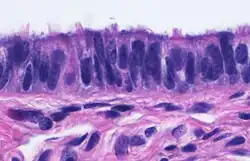

When viewed under the microscope, the fallopian tube has three layers.[6] From outer to inner, these are the serosa, muscularis mucosae, and the mucosa.[15][16]

The outermost covering layer of serous membrane is known as the serosa.[6] The serosa is derived from the visceral peritoneum.[14]

The muscularis mucosae consists of an outer ring of smooth muscle arranged longitudinally, and a thick inner circular ring of smooth muscle.[6] This layer is responsible for the rhythmic peristaltic contractions of the fallopian tubes, that with the cilia move the egg cell towards the uterus.[14]

The innermost mucosa is made up of a layer of luminal epithelium, and an underlying thin layer of loose connective tissue the lamina propria.[16] There are three different cell types in the epithelium. Around 25% of the cells are ciliated columnar cells; around 60% are secretory cells, and the rest are peg cells thought to be a secretory cell variant.[4] The ciliated cells are most numerous in the infundibulum, and the ampulla. Estrogen increases the formation of cilia on these cells. Peg cells are shorter, have surface microvilli, and are located between the other epithelial cells.[6] The presence of immune cells in the mucosa has also been reported with the main type being CD8+ T-cells. Other cells found are B lymphocytes, macrophages, NK cells, and dendritic cells.[16]

The histological features of tube vary along its length. The mucosa of the ampulla contains an extensive array of complex folds, whereas the relatively narrow isthmus has a thick muscular coat and simple mucosal folds.[14]

Cross-section of fallopian tube, stained and viewed under microscope